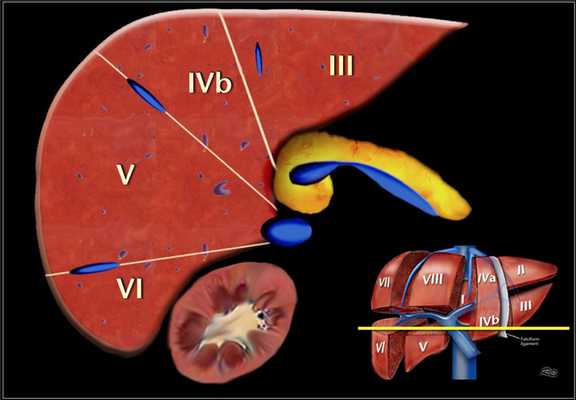

Аксиальное изображение верхних сегментов печени, которые разделены правой и средней печеночной веной и серповидной связкой. Изображение представлено ниже.

Это поперечные изображения на уровне левой воротной вены.

На этом уровне левой воротной вены делит левую долю в верхних отделах (II и IVa) и нижних сегментов (III и IV в).

Левая воротная вена находится на более высоком уровне, чем в правая воротная вена. Изображение представлено ниже.

Аксиальное изображение на уровне правой воротной вены. На данном срезе воротная вена делит правую долю на верхние сегменты ((VII и VIII) и нижние сегменты (V и VI).

Уровень правой воротной вены ниже уровня левой воротной вены. Изображение представлено ниже.

Аксиальное изображение на уровне селезеночной вены, которая находится ниже уровня правой воротной вены, видна только в низко лежащих сегментах. Изображение представлено ниже.